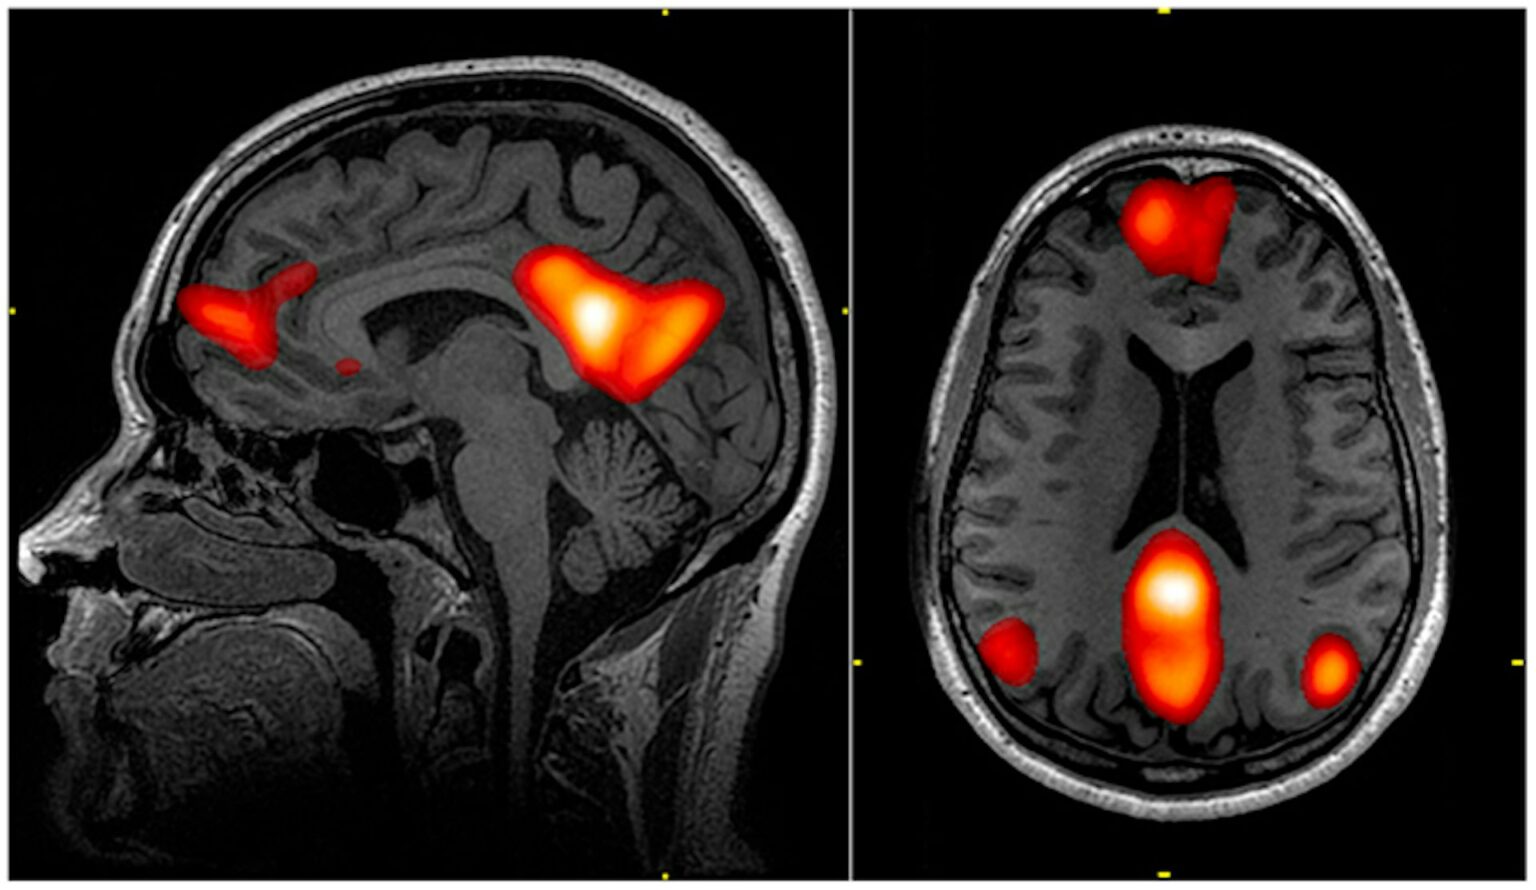

Πλήθος ερευνών σήμερα επιβεβαιώνει τα ευεργετικά αποτελέσματα του φυσικού περιβάλλοντος: μείωση του στρες, βελτίωση της προσοχής, καλύτερη διάθεση και γνωστική λειτουργία. Νευροαπεικονιστικές μελέτες δείχνουν πως η αμυγδαλή, ο εγκεφαλικός πυρήνας που σχετίζεται με το άγχος, εμφανίζει μειωμένη δραστηριότητα όταν εκτιθέμεθα στη φύση — κάτι που δεν παρατηρείται σε αστικά περιβάλλοντα.